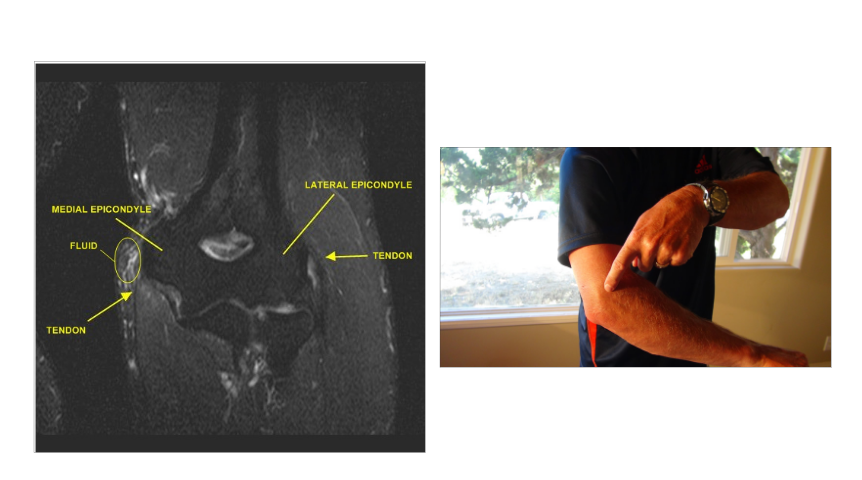

What is this?

Olecranon Bursitis

Olecranon Bursitis

- Who gets this?

- What is a bursa?

- DDx? 3

- Why shouldnt you drain it?

- First line?

- If you need to drain, Drain it where?

- Indications for removal? 3

- people who alternate from each elbow.

- Bursa- fluid filled sac- but no room besides the liquid layer.

- DD:

- RA (thicker, have other dz processes, rice bodies),

- septic bursitis,

- lipoma - Made of fluid producing cells so if you drain it will come back.

- COMPRESSION SLEEVE- keeps from irritating and helps drain: FIRST LINE especially for traumatic

- drain right along the triceps, don’t do it on the big bump

- Indications for removal:

- Drain fails

- Nerve damage

- Infection